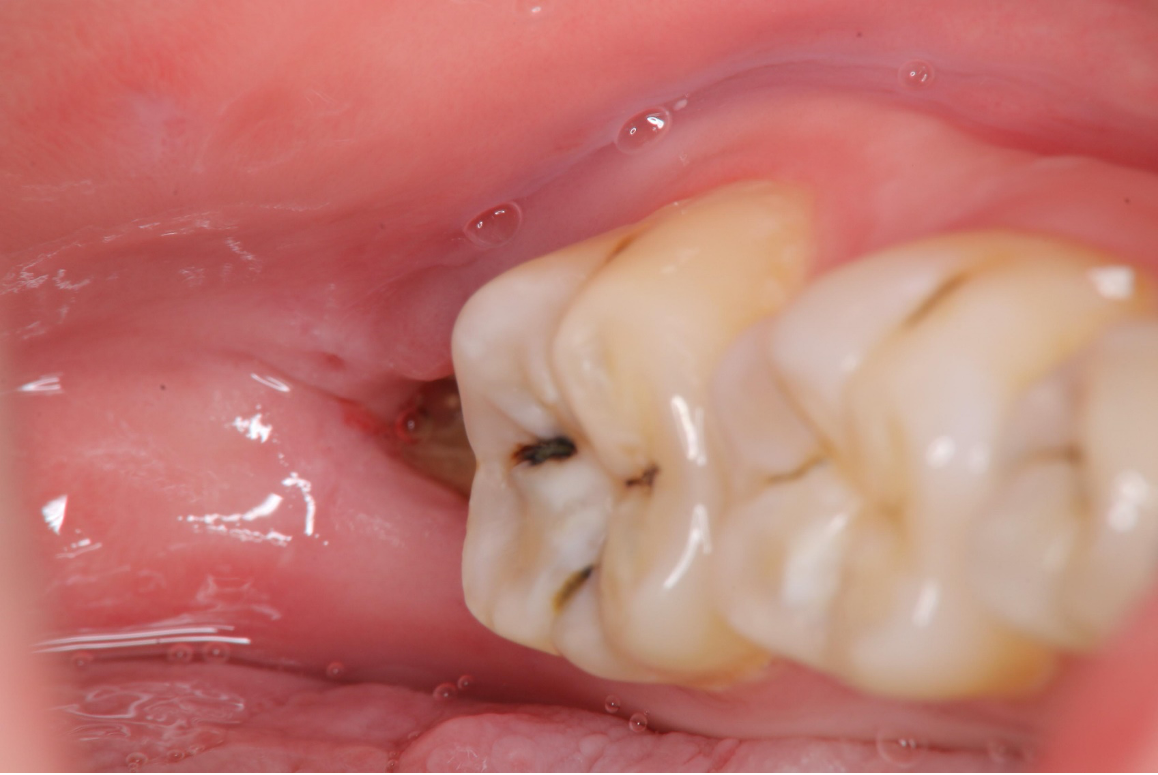

1週後傷口癒合良好